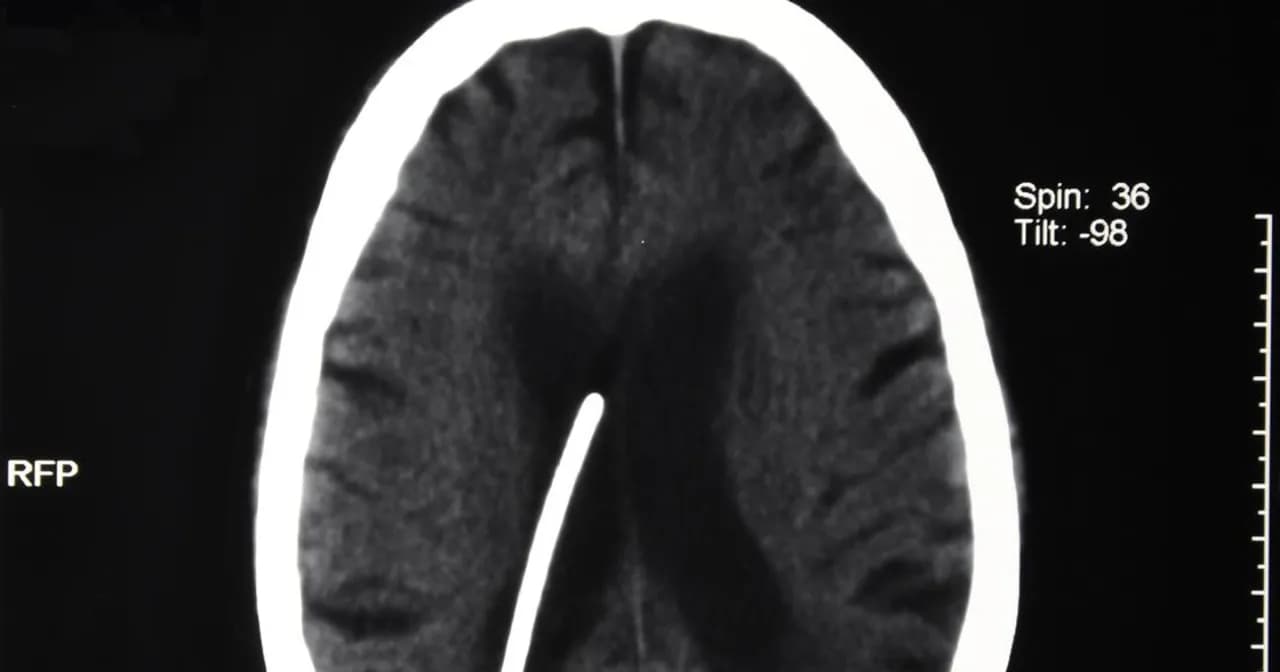

Wodogłowie u dorosłych objawy – jak je rozpoznać i uniknąć powikłań

Poznaj objawy wodogłowia u dorosłych, aby szybko je rozpoznać i uniknąć powikłań. Dowiedz się, jakie sygnały powinny budzić niepokój.